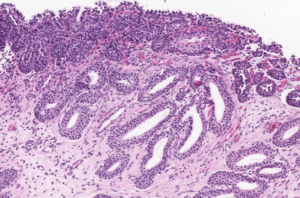

The polyps found in the bladder mucosa consist of a core of proliferative connective tissue covered by surface epithelium. This surface epithelium can form nests of hyperplastic urothelial cells in the lamina propria, known as Brunn’s nests, or undergo metaplasia to a mucus-secreting, glandular epithelial type, leading to a condition called CYSTITIS GLANDULARIS. These resulting polypoid masses may have a broad-based or pedunculated structure, occurring most frequently in the cranioventral bladder wall. Chronic haematuria, often unresponsive to antimicrobial therapy, is a common observation in cases of chronic polypoid cystitis. This bleeding is often associated with the breakdown of polyps, potentially promoting urine retention and bacterial introduction, thus establishing a cyclic pattern of infection, proliferation, and inflammation.

Histologically, our case had in lamina propria, occasionally extending from mucosa, multiple hyperplastic tortuous glands that were often cystic dilated. They were lined by one to multiple layers of uniform cuboidal or columnar epithelial cells, occasionally surrounded by a few layers of urothelial cells. They had no evident atypia. The lamina propria where they were immersed contained a few plasma cells, lymphocytes, neutrophils and rare histiocytes.